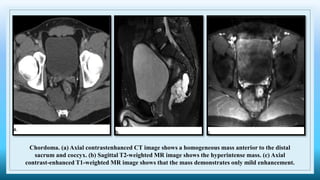

Chordoma. (a) Axial contrastenhanced CT image shows a homogeneous mass anterior to the distal

sacrum and coccyx. (b) Sagittal T2-weighted MR image shows the hyperintense mass. (c) Axial

contrast-enhanced T1-weighted MR image shows that the mass demonstrates only mild enhancement.